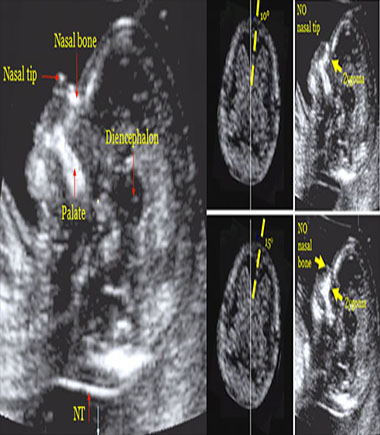

- Ecografía genética del primer trimestre (11 a 13.6

semanas): Permite detectar problemas fetales a través de marcadores ecográficos que sugieren

anomalías cromosómicas, congénitas y síndromes genéticos. Se tiene una alta tasa de detección (cercana al 95%)

con un bajo porcentaje de falsos positivos (2.5%). Es esencial para mujeres mayores de 35 años.